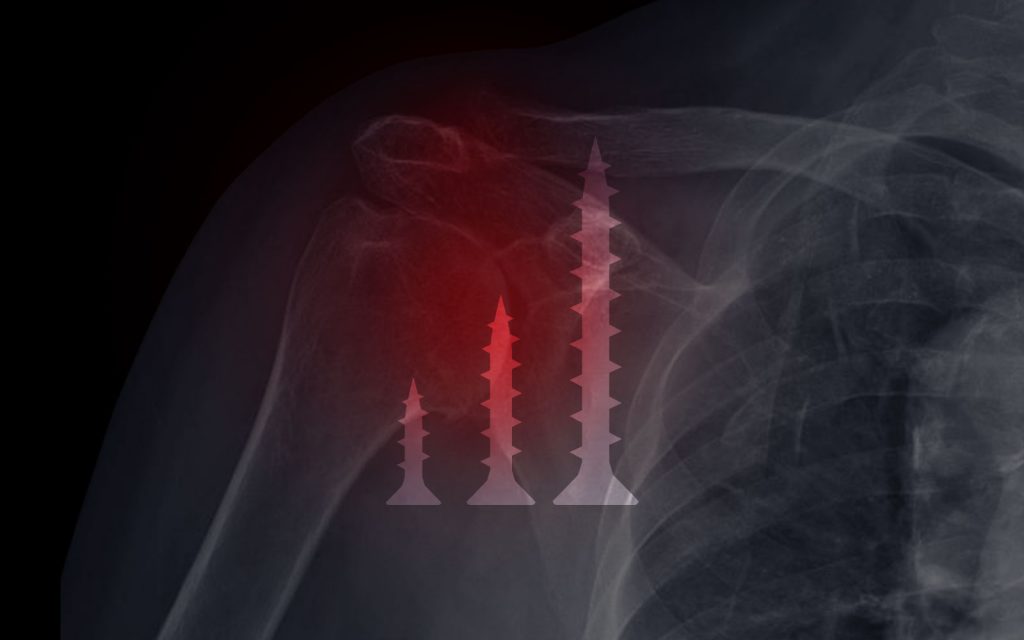

Roche et al in their recent article in JSES Open Access entitled “Impact of screw length and screw quantity on reverse total shoulder arthroplasty glenoid fixation for 2 different sizes of glenoid baseplates” evaluated how the number and length of screws affect baseplate fixation in an osteoporotic bone-substitute model using the Advita standard and the Advita small glenoid baseplates. They evaluated shear and compressive cyclic loading in a biomechanical model looking at constructs with two, four, and six screws with different screw lengths (18, 30, 46mm). All scenarios tested showed that the baseplates remained well-fixed after cyclical loading of 10,000 cycles without catastrophic failure, but there was a difference in displacement between the constructs. Baseplate displacement was less for the constructs with four screws compared to the constructs with two screws. The addition of six screws in the large baseplate did not make a difference in displacement. In addition, constructs with the longest screws had the lowest amount of baseplate displacement after cyclical loading. Short screws (18mm) showed the most displacement in both the small and standard baseplates.

This study is important for two main reasons. First, it demonstrates the importance of long screws when attempting adequate glenoid fixation in osteoporotic bone. While none of the constructs failed, displacement is a concern for long-term fixation. The better the constructs can withstand displacement, the less chance of loosening they will have. Obtaining longer screws with good fixation in rTSA can be difficult due to lack of intraoperative visualization of the glenoid vault. While preoperative planning and association with bony landmarks is critical for baseplate and screw placement, the ability to place the screws exactly where they are desired (to maximize length and fixation) is difficult. AdvitaGPS intraoperative computer navigation (Guided Personalized Surgery) gives surgeons the ability to place the screws intraoperatively exactly where they want within the glenoid vault to maximize screw length and fixation.

Secondly, this study also shows that increasing the number of screws decreases the risk of baseplate displacement. The downside of increasing the number of screws is that it increases the risk of scapular spine stress fracture4 as well as injury to the suprascapular nerve.5 In addition, just placing four screws, even though one or two may not have good fixation, does not likely add much to a construct in which two or three long screws with good fixation are present. This study showed that longer screws may substitute for more screws in regard to initial baseplate fixation in osteoporotic bone. In my experience, intraoperative computer navigation allows me to place screws in the best bone available and in the appropriate trajectory to have longer screws which, therefore, leads to better fixation with less screws. The screw orientation that I use with computer navigation differs from my preoperative plan commonly, especially in glenoids with severe wear or when baseplate augments are used. In addition, I avoid any screws or screw orientations that exit anywhere near the spinoglenoid notch to avoid contact with the suprascapular nerve or its branches.

Decreasing the number of screws by optimizing the screw trajectory and fixation can lower total implant cost, potentially decrease injury to branches of the suprascapular nerve, and potentially decrease scapular spine fracture stress risers. This study validates what I suspected about the number and length of screws used in baseplate fixation. Currently, I commonly use two or three long screws with excellent fixation placed with the assistance of computer navigation. Gaining knowledge regarding baseplate fixation is important to understand how surgeons can minimize complications regarding baseplate placement. More research is necessary to understand how increasing the length of screws and decreasing the number of screws affects the long-term rTSA clinical outcomes and complication rates.